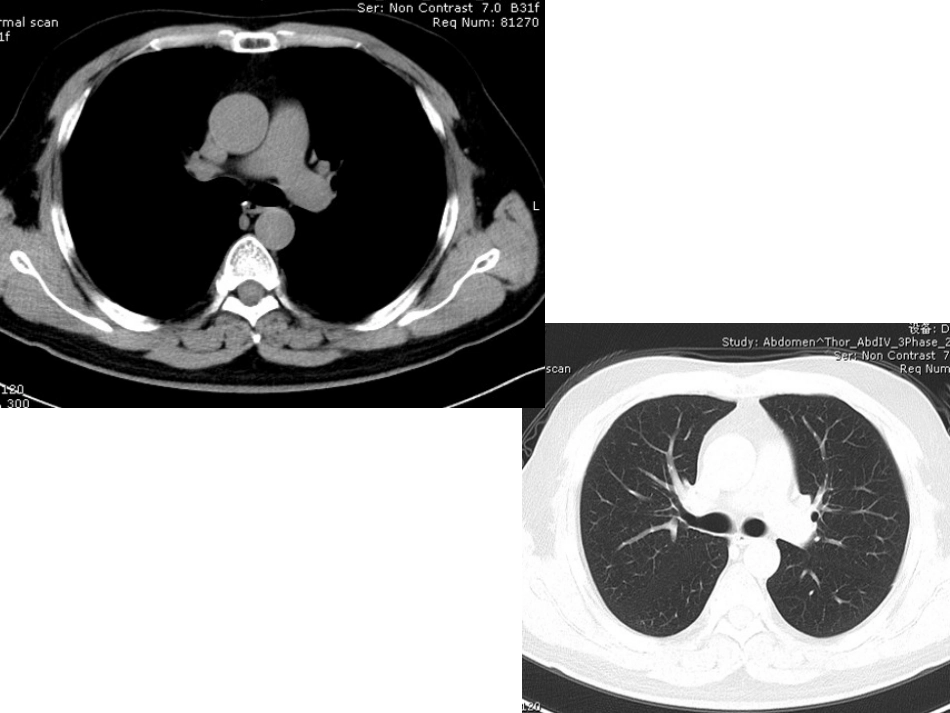

影像学考试试题